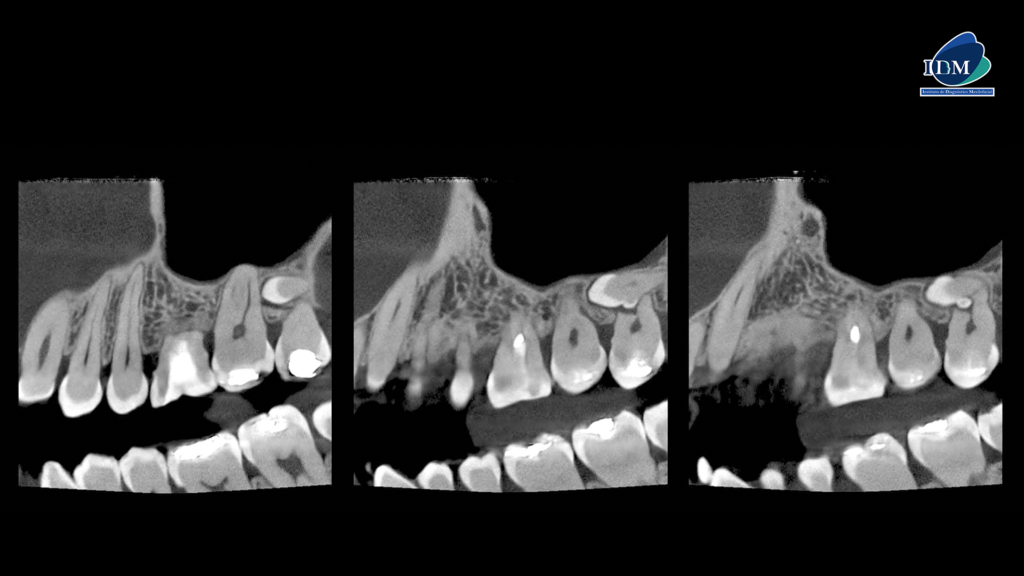

En el estudio ampliado mediante tomografía computarizada de haz cónico (TCHC), se observa una pieza dentaria supernumeraria localizada en posición vestibular respecto a la raíz de la pieza 28. La corona de esta pieza supernumeraria está en contacto con la raíz distovestibular de la pieza 27, según se aprecia en los cortes axiales. Asimismo, se identifica una anomalía de desarrollo en dicha pieza supernumeraria, compatible con perla del esmalte en su región cervical, la cual está asociada con reabsorción radicular externa de la pieza 28, observada en los cortes tangenciales y transaxiales.

CORTES TANGENCIALES